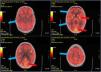

F18-FDG PET-TC cerebral con presencia de hipometabolismo cortical generalizado.

Tomografía por emisión de positrones con F18-fluordesoxiglucosa fusionado con TC cerebral. Se aprecia un hipometabolismo generalizado difuso en la corteza cerebral (flechas azules), con mayor captación de trazador en los ganglios de la base que en la corteza, así como algunos focos corticales occipitales con captación normal del trazador (flechas rojas).